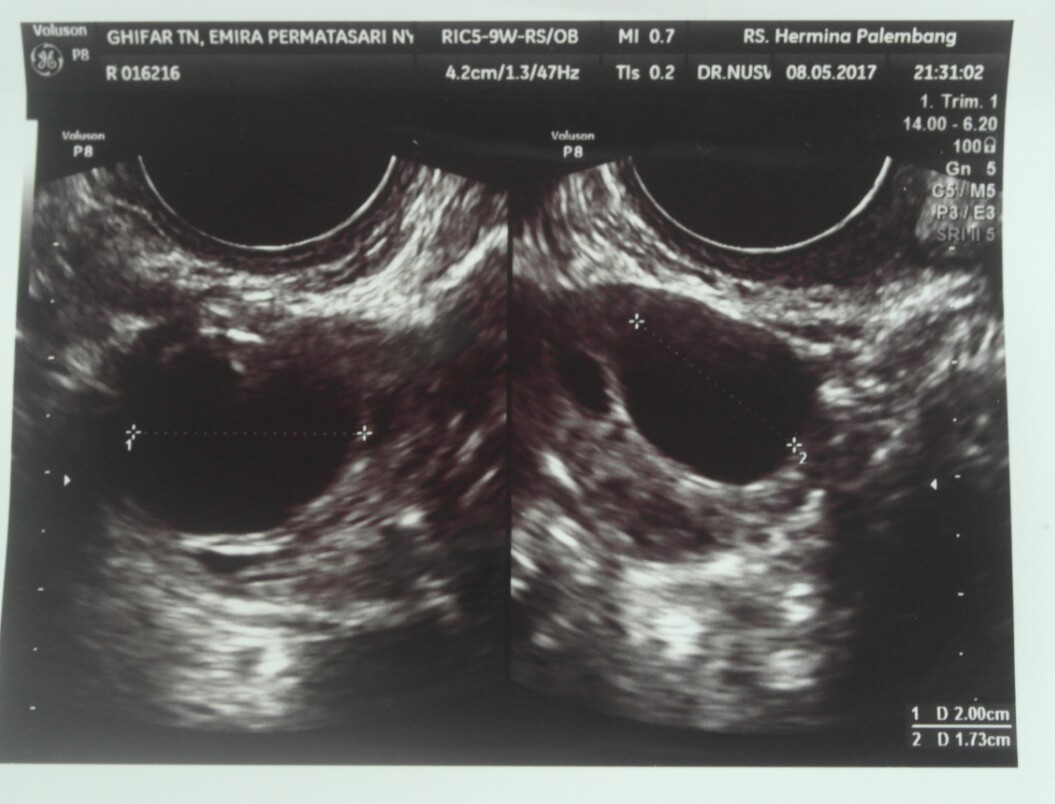

Gambar Usg Sel Telur Matang

BEGINI GAMBAR SEL TELUR YANG SUBUR… - dr Yudhistya SpOG | Facebook Story of My Journey: TTC Journey #2 USG Folikel dan Hasil Analisa Sperma Aku dan PCOS (Hasil USG Trans Vaginal) - JalanSenja.com Cerita Promil 4 - Polycystic ovary (PCO) - Fika Putri Cerita Promil 2 - USG Transvaginal dan Tes Sperma - Fika Putri Semua Akan Terjawab di Waktu yang Tepat - kumparan.com Promil Story : MIMPI BURUK ITU BERNAMA PCOs - The Arsalan Family Journal Penting Dilakukan Wanita, Ketahui Sel Telur Dalam Tubuhmu Jangan Sampai “Mandul” Karena Kehabisan Program Hamil di Dokter Lusiana Irene, SpOG Jogja Manusia sedikit tahu..sel telur kecil tidak mungkin hamil | Dr Suryo, SpOG - Kesehatan Reproduksi C e r i t a C i k i: Sel Telur Kecil-Kecil EFEK PENYUBUR Pada wanita normalnya sel… - dr Yudhistya SpOG | Facebook Ikhtiar yang ke dua – Part 2 (H6-H11) – Bread and Butter Letter Promil Step 4 – Baby Journey PCOS adalah… | Kisah Ibuknda (pakai ‘k’) :D Room | ‘Aisyah Tsurayya Inart’s Story - Yah, Saya Akhirnya Hamil - I’m 1 In 10: My PCOS Story Kisah Perjuangan Terbaru Tya Ariestya Saat Jalani Program IVF | Popmama.com story of my lyfe: pejuang keturunan Nikita Mirzani Bagikan Hasil USG Bayi Kembar, Dapatkah Gen Kembar Diturunkan? - Semua Halaman - Intisari lihat hasil USG tranvaginalku wktu bulan Januari 2013 apa itu PCO? - IbuHamil.com Cerita Promil 4 - Polycystic ovary (PCO) - Fika Putri aq PCO bund, ada yg bisa bantu baca hasil USG intravagina q??? - IbuHamil.com Hasil USG Sel Telur Yang Subur - YouTube Pengalaman Bayi Tabung/ IVF (Part II) Update with Pict! | honeymenulis’s Blog Inart’s Story - Yah, Saya Akhirnya Hamil - Story of My Journey: June 2017 Ingin Terhindar dari Kista? Jauhi 4 Jenis Makanan Enak Ini Sekarang! - Semua Halaman - Grid Health Program Hamil Bulan ke-1 : PCOS Survivor | Lanalouie Embrio 3 cm berapa minggu. minggu: bayi Anda sebesar tongkol jagung BEGINI GAMBAR RAHIM YANG SUBUR… - dr Yudhistya SpOG | Facebook PCOS | medicalstudentnotes USG Transvaginal: Penjelasan, Prosedur & Manfaat (Lengkap) | Friso BILIK SONOGRAFER : Kista Ovarium Kontrol H+10 (Cek Perkembangan Sel Telur) Istilah kehamilan dipertimbangkan dengan USG. Kehamilan kebidanan dan embrio Selamat Pagi Senin Ayah Bunda. Semoga… - Dokterkandungan. id | Facebook My First USG | Story of Us Menuju Hamil – Part 2 of 3 – Edward Suhadi Apa itu PCOS? Kenapa Sulit Hamil? | Sunshine of My Life Setiap Ibu Hamil Harus Tahu, Kapan Harus Melakukan USG lewat Vagina? - Semua Halaman - Nakita Program Hamil di Dokter Lusiana Irene, SpOG Jogja Saat Sel Telur Berukuran Kecil dan Sulit Dibuahi - Health Liputan6.com Kabar Gembira, Ini Tanda Awal Sel Telur Berhasil Dibuahi oleh Sperma | Popmama.com 101+ Gambar Cek Sel Telur Paling Hist - Gambar Pixabay Kontrol H+12 (Mendebarkan, apakah sel telurnya tetap berkembang?) Program Kehamilan Balasan dari Saya Penderita PCOS, Saya Berhasil Hamil | KASKUS Pembekuan Sel Telur: Fungsi, Prosedur, dan Komplikasi INGIN HAMIL – Siklus Ovarium dan Tanda-Gejala Wanita Subur | JuliantoWitjaksono.com 6 Fakta Mengejutkan Tentang Sel Telur Wanita - YouTube Pengalaman Hamil Kembar - The Urban Mama Maimuns — PCOS? Deal with it! Berapa Sisa Sel Telur di Tubuh? Bisa Dicari Tahu | Parenting.Dream.co.id PCOS Polycystic Ovary Syndrom Apakah… - Komunitas Impian Bunda | Facebook Persiapan Hamil (4) – jurnal Ammi Wanita Hasilkan 2 Sel Telur dalam Masa Ovulasi, Bisakah Terjadi? Promil Story : MIMPI BURUK ITU BERNAMA PCOs - The Arsalan Family Journal My journey to motherhood: HSG, Tes Sperma, hingga PCO Polikistik Ovarium (PCOS): Haid sering tidak datang, Berkumis, Berjerawat, Ingin hamil sulit | Dr Suryo, SpOG - Kesehatan Reproduksi PCOS dan Metformin. Sohib karib! – Cerita Bumi Blighted Ovum | ~cahaya kebaikan~ Cerita Pengalaman Kehamilan Pertama dan Persiapan Melahirkan Anak Pertama - For The Love of Foods and Beauty Masih banyak yg belum tau.. INSEMINASI… - Bayi Tabung PMC Pekanbaru Cerita Program Hamil dengan Dokter Enny Sp.OG di Yogyakarta ~ Land of Jenganten Semua Akan Terjawab di Waktu yang Tepat - kumparan.com Fika Putri Berbagi Tips: Cara Mengetahui Masa Subur Wanita Berdasar Penghitungan serta Ciri-Cirinya - Garda Remaja GAGAL OVULASI?? SERING TERJADI PADA… - Konsultasi Promil Cepat Hamil dan Alami | Facebook Yosevina Issabela prosespersalinan Instagram posts (photos and videos) - Picuki.com Apa sebetulnya bayi tabung dan bagaimana proses menjalaninya? – Bayi Tabung Penang Di minggu kebidanan mana embrio terlihat. Minggu berapa embrio terlihat pada USG? Apakah prosedurnya aman pada tahap pembentukan anak PCOS itu Variable dan Sangat Rumit Prosedur Bayi Tabung: Sebelum dan Sesudah Mengikutinya - Smarter Health Mengenal Kehamilan Kosong atau Blighted Ovum (BO) - Kompasiana.com Cerita Promil, Perjalanan menuju kehamilan (long story short, I finally got pregnant) - Nyonyah Intan Sindrom Ovarium Polikistik (PCOS) 4D Gallery | Dr Suryo, SpOG - Kesehatan Reproduksi Kapan USG direncanakan selama kehamilan. Apakah saya perlu mempersiapkan prosedur? Keadaan organ reproduksi wanita Irish Bella Hamil Anak Kembar, Sang Ibunda Tak Sangka Bakal Punya 2 Cucu - Halaman all - Tribun Batam Lapsus Kista Ovarii - Apriamalia - [PDF Document] Success story – GLADIOOL IVF RS Indosehat Solo, Jl Solo Sragen Km 11, Kebakramat, Karangdawa (2020) Saya Penderita PCOS, Saya Berhasil Hamil | KASKUS September 2014 - Pipit Widya Aku dan PCOS (Hasil USG Trans Vaginal) - JalanSenja.com Pengalaman PCOS-ku yang Berhasil Hamil Alami - kumparan.com Apakah USG mempengaruhi kehamilan. Bagaimana ultrasound mempengaruhi embrio? Ultrasonografi dilakukan hanya atas kesaksian dokter atau mungkin atas permintaan ibu BAB III - [DOCX Document] Kista Ovarium. - ppt download Biaya USG 3 & 4 Dimensi di Karawang - Perawatan Kesehatan Cerita Pengalaman Kehamilan Pertama dan Persiapan Melahirkan Anak Pertama - For The Love of Foods and Beauty Wanita Punya 400 Sel Telur Setiap Menstruasi, Kenapa Susah Hamil? - Semua Halaman - Nakita Tragis Si Ibu Hamil Dibunuh, Bayi di Dalam Kandungan Dicuri - Halaman all - Warta Kota Perlukah USG Transvaginal saat Program Hamil? | Popmama.com 13 Tanda - tanda Kehamilan Awal yang Bisa Dipercayai - Mamapapa.id Melahirkan bayi kembar pada minggu-minggu kehamilan. Dapatkah dokter tidak melihat bayi kembar dengan USG: diagnosis dini kehamilan ganda PROSES DAN BIAYA INSEMINASI 1. USG USG… - dr Yudhistya SpOG | Facebook